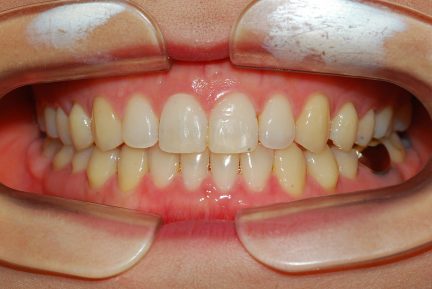

État final

- Relation de Classe I obtenue

- Guidage fonctionnel des canines des deux côtés

- Surplomb et recouvrement normaux obtenus

- Ligne esthétique du sourire obtenue

- Cas où tous les objectifs de traitement ont été atteints

- J'ai été impressionné par les effets remarquables observés en peu de temps sur ce cas utilisant Invisalign.

Surtout après la fermeture d'espace, le contrôle de l'inclinaison linguale buccale des dents antérieures inférieures était excellent.